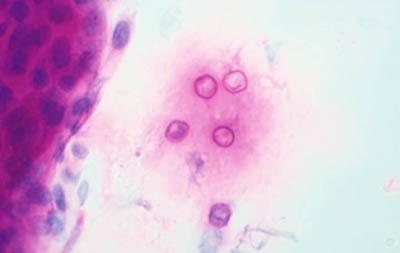

A - CW B - Giemsa C - PAS D - Gram

Tinción PAS

(Acido Periodico de Schiff)

Magnificación 160x

Magnificación 160x